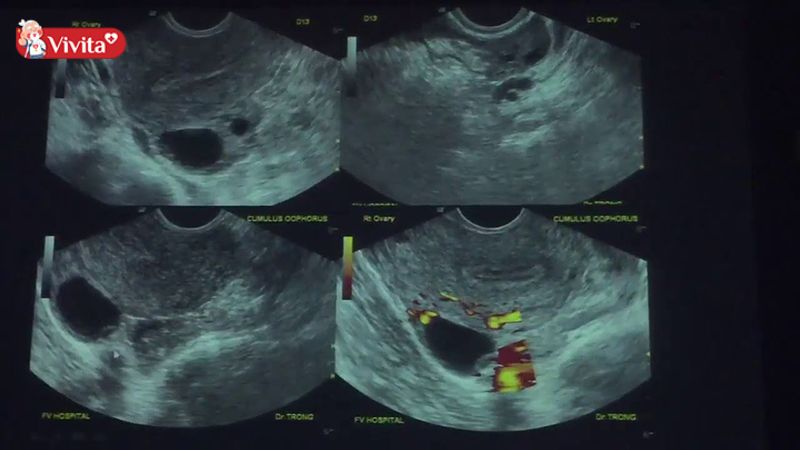

Siêu âm để xác định ngày rụng trứng

Siêu âm nang noãn là phương pháp y khoa đáng tin cậy để xác định chính xác thời điểm rụng trứng. Bác sĩ sẽ theo dõi sự phát triển của nang trứng trong buồng trứng và dự đoán thời điểm trứng sẽ phóng thích.

Phương pháp này thường được áp dụng cho những phụ nữ có chu kỳ kinh không đều, đang gặp khó khăn trong việc mang thai hoặc cần lên kế hoạch thụ thai nhân tạo.